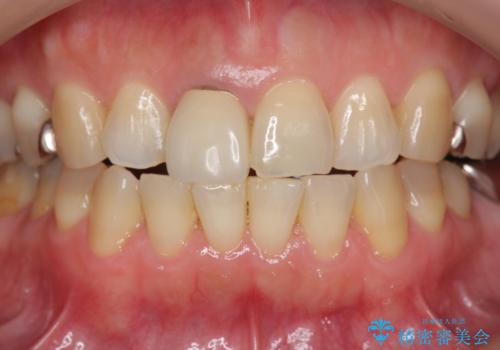

セラミッククラウン 歯ぐきの黒ずみの改善

- 十数年前に治療した前歯のクラウンの歯ぐきの位置が変化し、黒いラインが見え審美性の改善を求めて来院されました。

ファイバーコアのやりかえを行ったのち、金属を用いないジルコニアクラウンによる再補綴を行い前歯の審美性の向上を計画します。

近年前歯のクラウン製作に用いられるジルコニアクラウンは、金属を用いていないため経年的に歯ぐきの位置が変わっても黒いラインが見えることなく審美性の意地が期待できます。